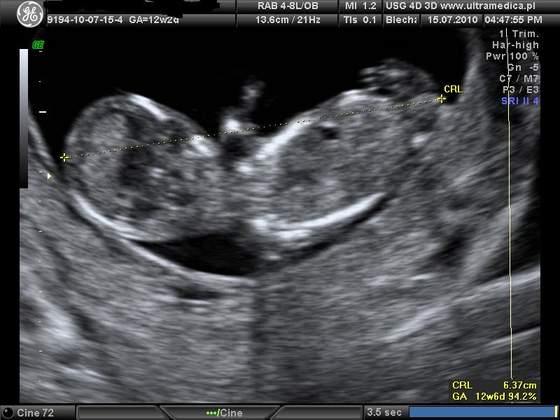

A ja dzisiaj byłam na usg. Okazało sie, ze maluszek jest o tydzien starszy niz na suwaczku, 13t5d, ma 7,7 cm wzrostu

Wrazenie naprawde niesamowite. Na poczatku maluszek spal, pozniej lekarz go budzil mocniej naciskajac brzuch. Zaczal machac raczkami, robic fikołki. Pozniej sie juz uspokoil, zaczal ssac paluszka i dal sie zmierzyc lekarzowi

Takze jestem dumna z mojego dzidziusia. Wszystko jest w porzadku wrecz ksiazkowo. Dostalismy kilka zdjec i płyte CD. Oczywiscie byl ze mna narzeczony. A co najlepsze znamy płeć

a oto ON: